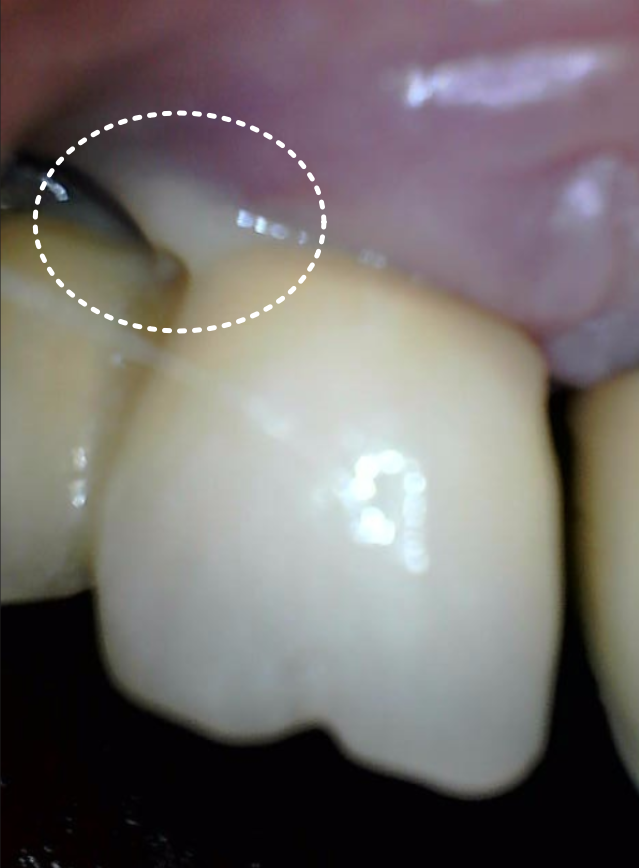

맨 끝 쪽 임플란트(#37) 주변 잇몸에서

고름이 새어 나오고 있었고

잇몸 밖으로 임플란트 뿌리가

드러나 있었습니다.